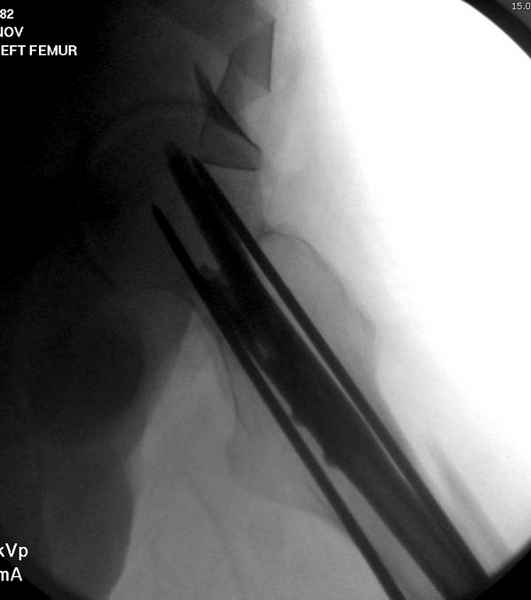

Учитывая, что случай ургентный, больной поступил вечером, не стали делать вытяжение и срочно провели операцию по фиксации перелома бедра антеградным штифтом Versa Nail от DePuy.

Для профилактики дальнейшего раскола в шейке предварительно во время проксимального рассверливания спереди и сзади провели временные спицы, которые в дальнейшем были заменены на шурупы (miss nail method)